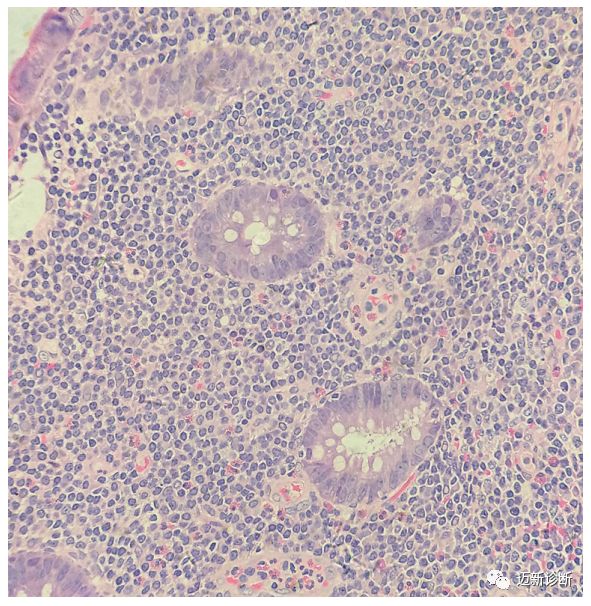

图23 黏膜相关淋巴组织(malt)淋巴瘤单核细胞增殖

8例肠黏膜相关淋巴组织淋巴瘤的临床病理特征

降结肠环形黏膜隆起镜下这么多淋巴细胞是单纯炎症可能吗?